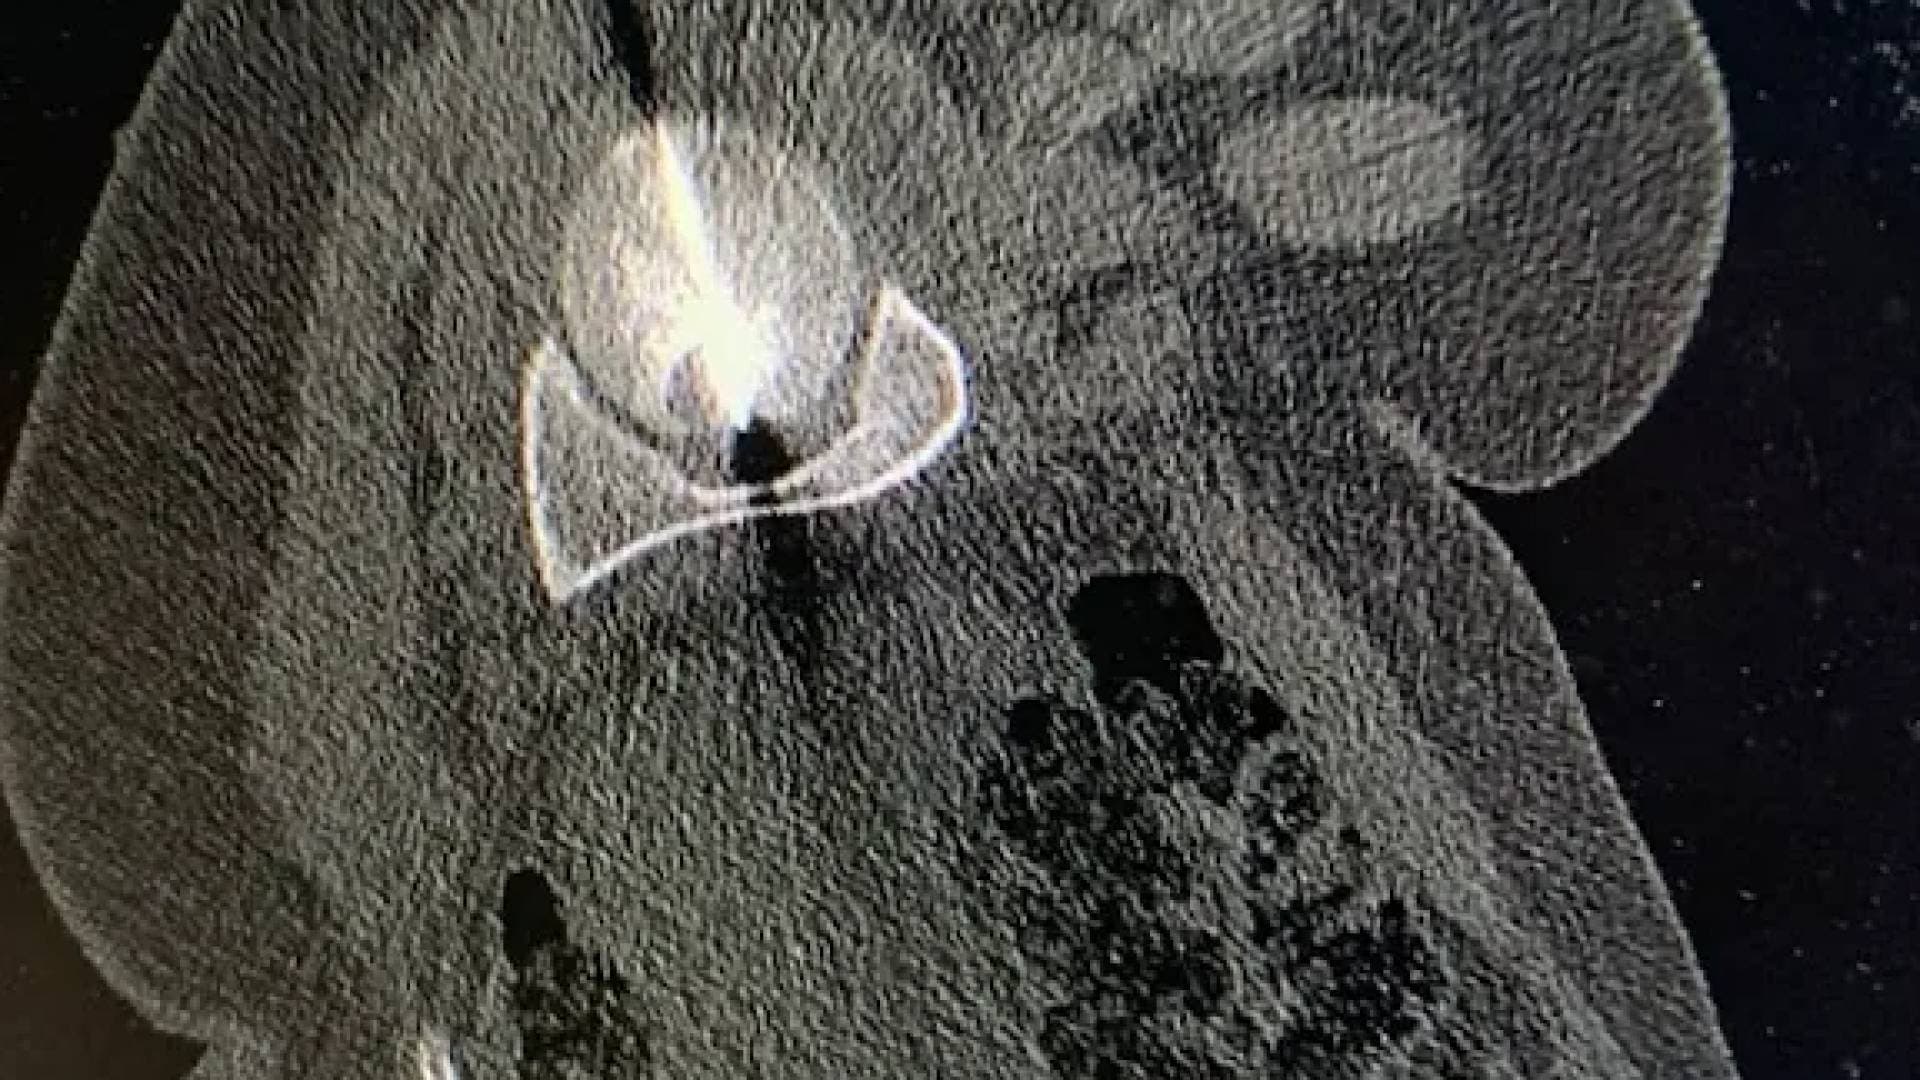

نجح فريق جراحة الأطفال في مستشفى الجامعة الأردنية في التعامل مع حالة طبية نادرة لطفل يبلغ من العمر تسع سنوات، كان يعاني من أكياس مائية ضخمة في الرئتين معا، وذلك من خلال تدخلين جراحيين دقيقين أجريا باستخدام تقنية المنظار الصدري، في إنجاز يسجل ضمن الحالات القليلة المشابهة على المستوى الطبي.

وتكمن خصوصية هذه الحالة في أن الأكياس المائية غالبا ما تظهر في الكبد وقد تمتد لاحقا إلى الرئتين، في حين يعد وجودها بشكل مباشر ومتعدد في كلتا الرئتين، وبأحجام كبيرة، أمرا نادر الحدوث. وقد جرى اكتشاف الحالة صدفة، رغم غياب أعراض واضحة، خلال فحوصات أجرتها استشارية أمراض الجهاز التنفسي والصدر للأطفال الدكتورة إيناس الزيادنة، بالتعاون مع فريقها الطبي.

وساعد استخدام تقنيات المنظار، المعتمدة على شقوق جراحية صغيرة، في تسريع تعافي الطفل بعد العملية الأولى التي أجريت للرئة اليمنى، ما أتاح تنفيذ العملية الثانية للرئة اليسرى بعد نحو أسبوعين فقط وبالأسلوب الجراحي نفسه. وقد غادر الطفل المستشفى خلال فترة قصيرة، مع متابعة طبية استمرت لعدة أشهر أكدت تماثله الكامل للشفاء وعودته إلى حياته اليومية دون أي آثار جانبية.